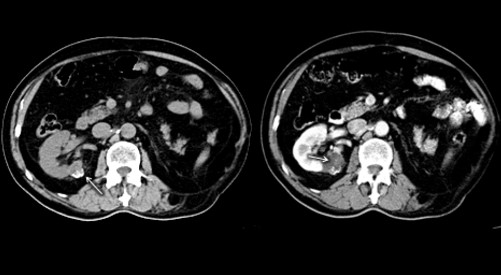

La Categoría IIF exhibe múltiples septos finos en su interior, realce evidente en paredes o septos, mínimo grado de engrosamiento de la pared, calcificación grosera o nodular, lesiones intra renales densas sin realce o con realce de septos o pared, siendo este realce no medible en las lesiones descubiertas con incremento de la densidad radiológica cuando se comparan las imágenes sin y con contraste yodado IV. Se consideran masas quísticas moderadamente complicadas y precisan seguimiento con controles cada seis meses.(19, 20) No requieren tratamiento quirúrgico inmediato y el riesgo de evolucionar a quistes malignos es del 5%, quistes con aspecto hiperdenso > 3 cm (Anexos 7 y 8).

La Categoría III muestra engrosamientos lisos o irregulares de la pared o de los septos intra quísticos y existencia de realce medible en TC y RMI. Se consideran masas indeterminadas y precisan de primera instancia cirugía, nefrectomía parcial o ablación por radiofrecuencia, salvo contraindicaciones clínicas.(19, 21) Aproximadamente el 40%-60% son lesiones malignas (carcinomas renal quístico), siendo el restante benignas, que incluyen quistes hemorrágicos, infectados crónicos o calcificaciones parietales, nefrona quístico multiloculado, quistes multilobulados, quistes con tabiques complejos, etc. (Anexos 9 y 10).